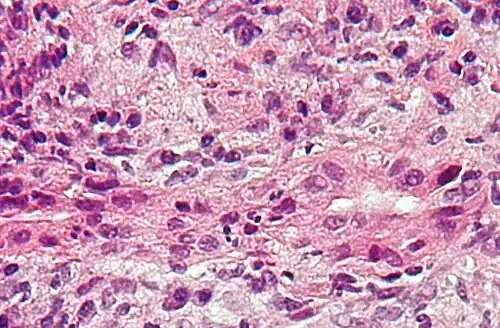

Mikrofoto einer primär biliären Zirrhose (HE-Färbung, mittlere Vergrößerung).

Mikrofoto einer primär biliären Zirrhose (HE-Färbung, mittlere Vergrößerung). -